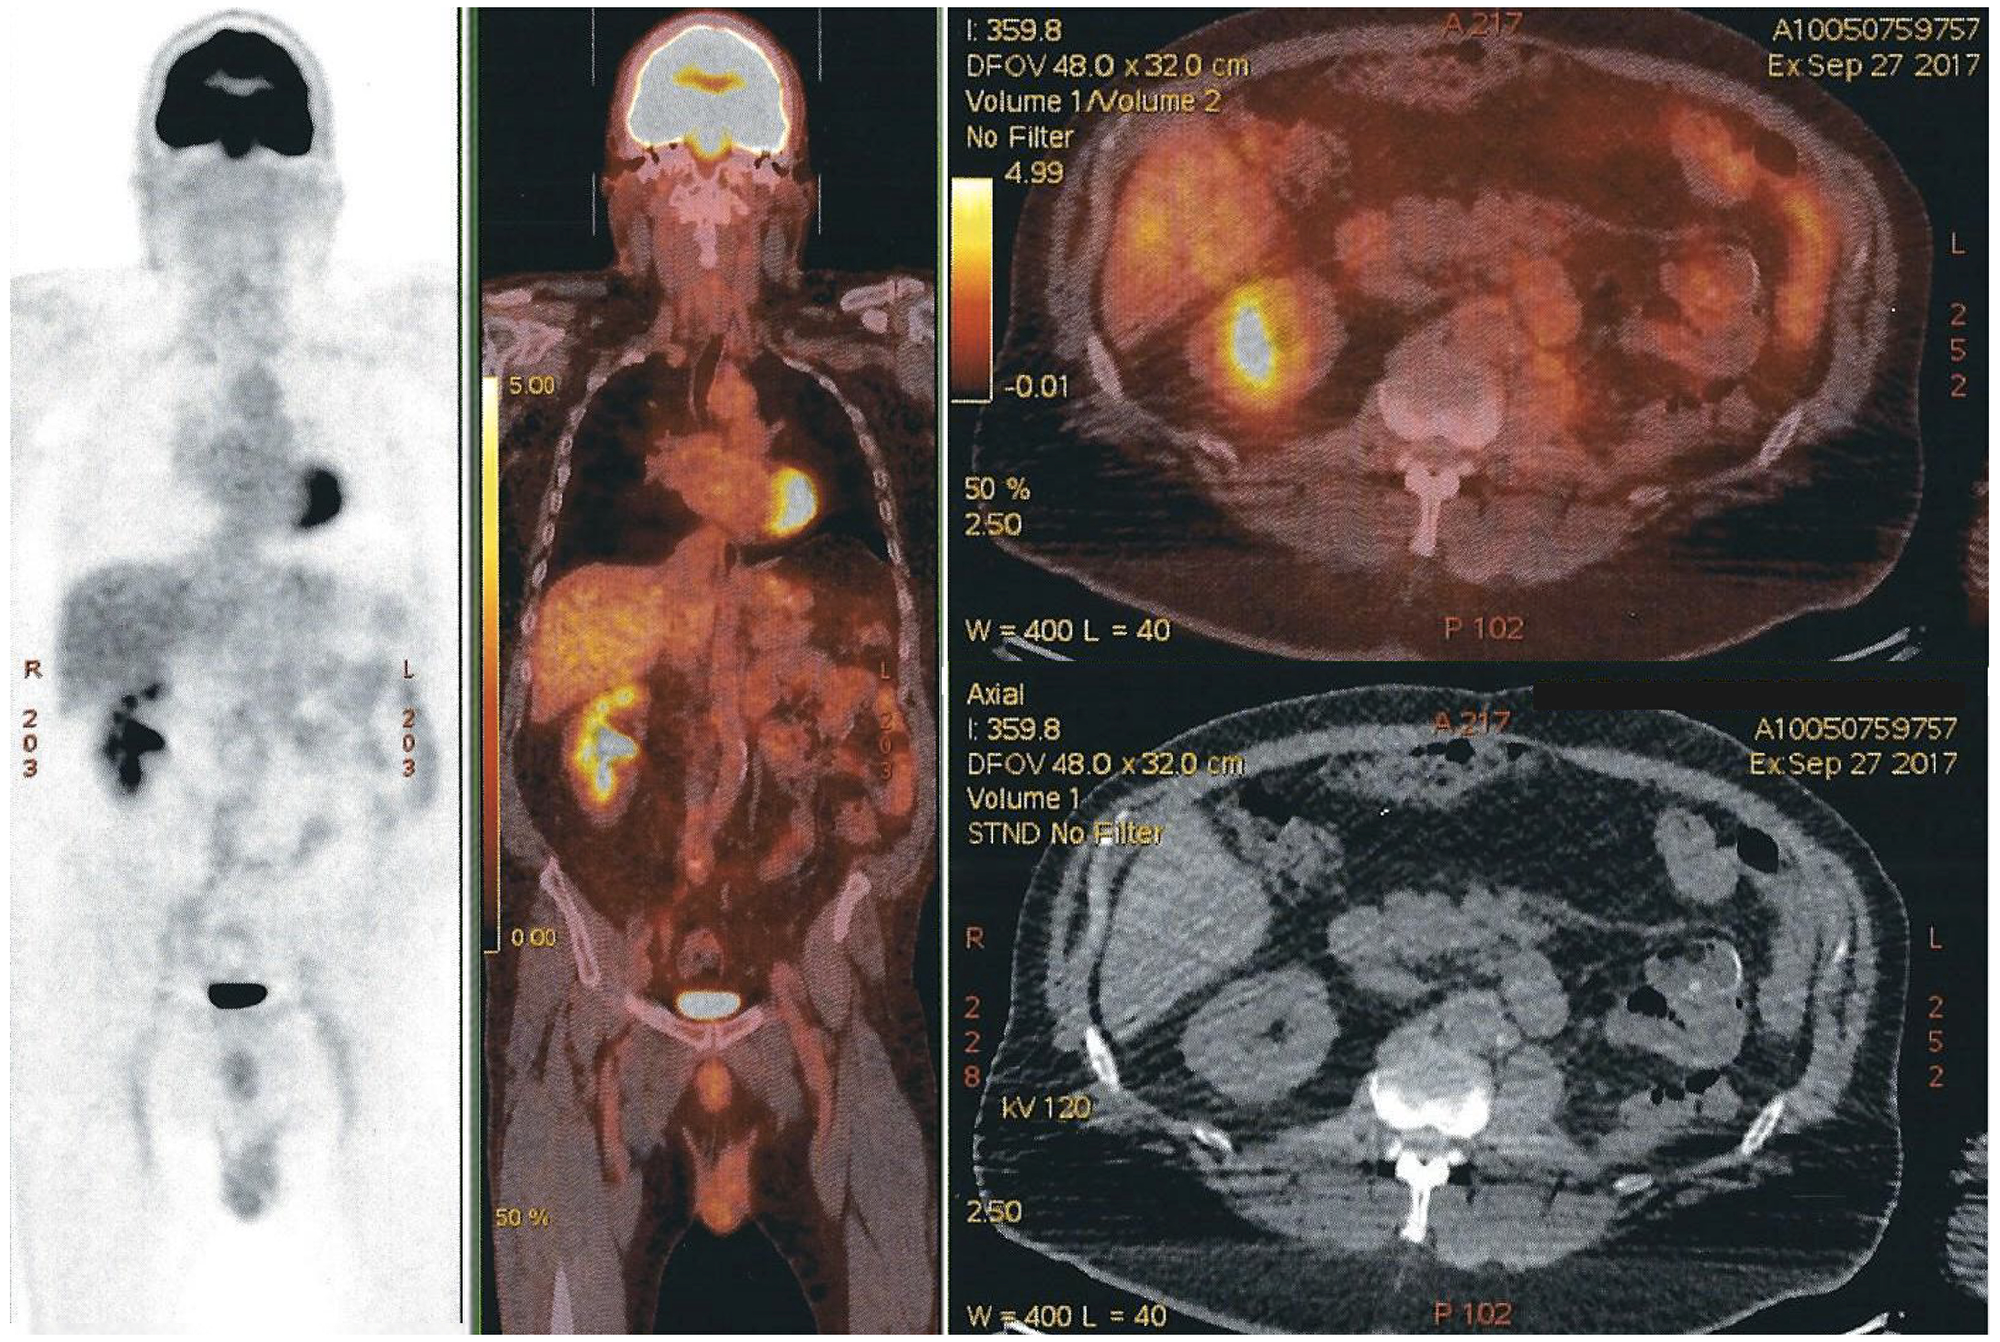

Four months later, a PET-CT scan was done and showed multiple retroperitoneal, pelvic and abdominal lymph nodes (Figure 5).

Figure 5: PET-CT Scan showing multiple retroperitoneal, pelvic and abdominal lymph nodes.

PET-CT scans done 4 and 8 months later, showed no evidence of recurrence of oncologic disease (Figure 6).

Figure 6: PET-CT scan with no evidence of recurrence of oncologic disease. Free left renal-bed, absence of distal lymph nodes, and nonexistence of any new suspect lesion. The modified area on the right side of the image is a shape added to cover the name of our patient.